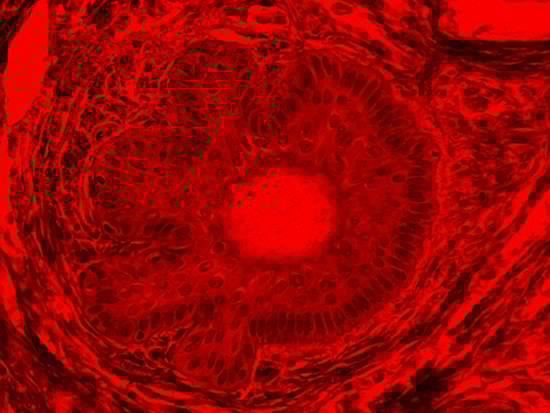

Figure 4: Brightfield Image of Dermal Tissue filtered with Red

When comparing Figure 3 with Figure 4, there is once again a significant visual difference. The most obvious feature is the change in color from green to red due to a different hardcoated filter being positioned in the optical path. The less obvious difference is the varying contrast levels caused by the filters at specific regions of the dermal tissue. For example, Figure 3 exhibits a distinct ring at the central region of the cell with additional matter within. In Figure 4, the ring is extremely faint and the internal matter is not visible. With that said, the cell and surrounding dense materials are more evident in Figure 3, whereas the muscle fibers and collagen are more pronounced in Figure 4.